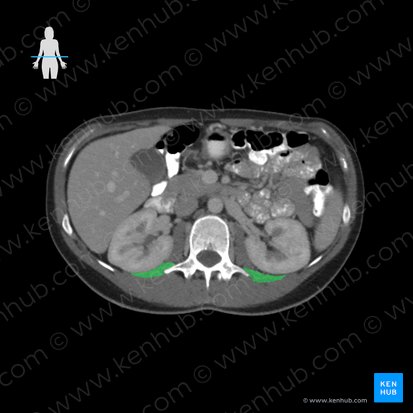

Topographie

Der Quadratus lumborum füllt einen großen Raum des Abdomen aus und steht daher in enger Nachbarschaft mit vielen Strukturen. Das Colon, die Nieren und das Zwerchfell befinden sich ventral des Muskels, dorsomedial liegt die autochthone Rückenmuskulatur. Sowohl der Nervus iliohypogastricus als auch der Nervus ilioinguinalis verlaufen nach Austritt aus dem Plexus lumbalis auf der ventralen Fläche des Quadratus lumborum entlang und ziehen weiter in Richtung der seitlichen Bauchwandmuskulatur.